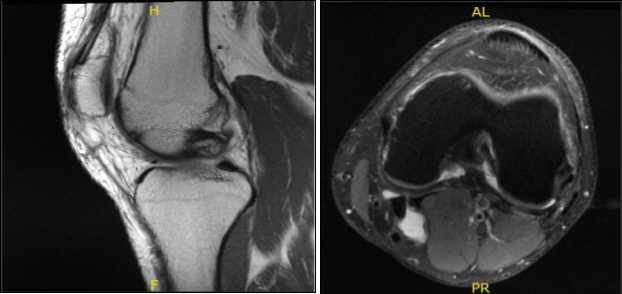

MRI results were presented today and showed lateral meniscal tear. Mild partial-thickness cartilage loss along the central trochlear groove and in the lateral compartment. Trace left knee joint effusion and small Baker’s cyst.

MRI-3T Left Knee Non-contrast